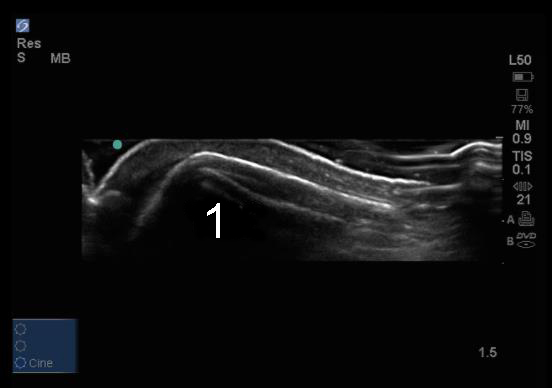

Elbow Olecranon Process No Bursitis Image

Olecranon Process